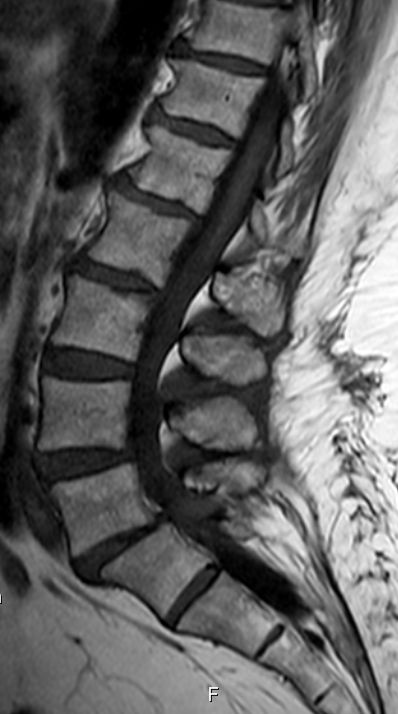

| Knochen | 12. BWK, MRT-T2-Bild![]() | Häufig in Wirbeln. Im MRT Verwechselung mit Tumoren und Metastasen möglich. | |

| Das Blut bewegt sich im Haemangiom sehr langsam. Dadurch im T1 und im T2-Bild sehr hell. Ausnahme: 2-4% Fast-Flow-Haemangiome. Im T2-Bild schwarz. | |||